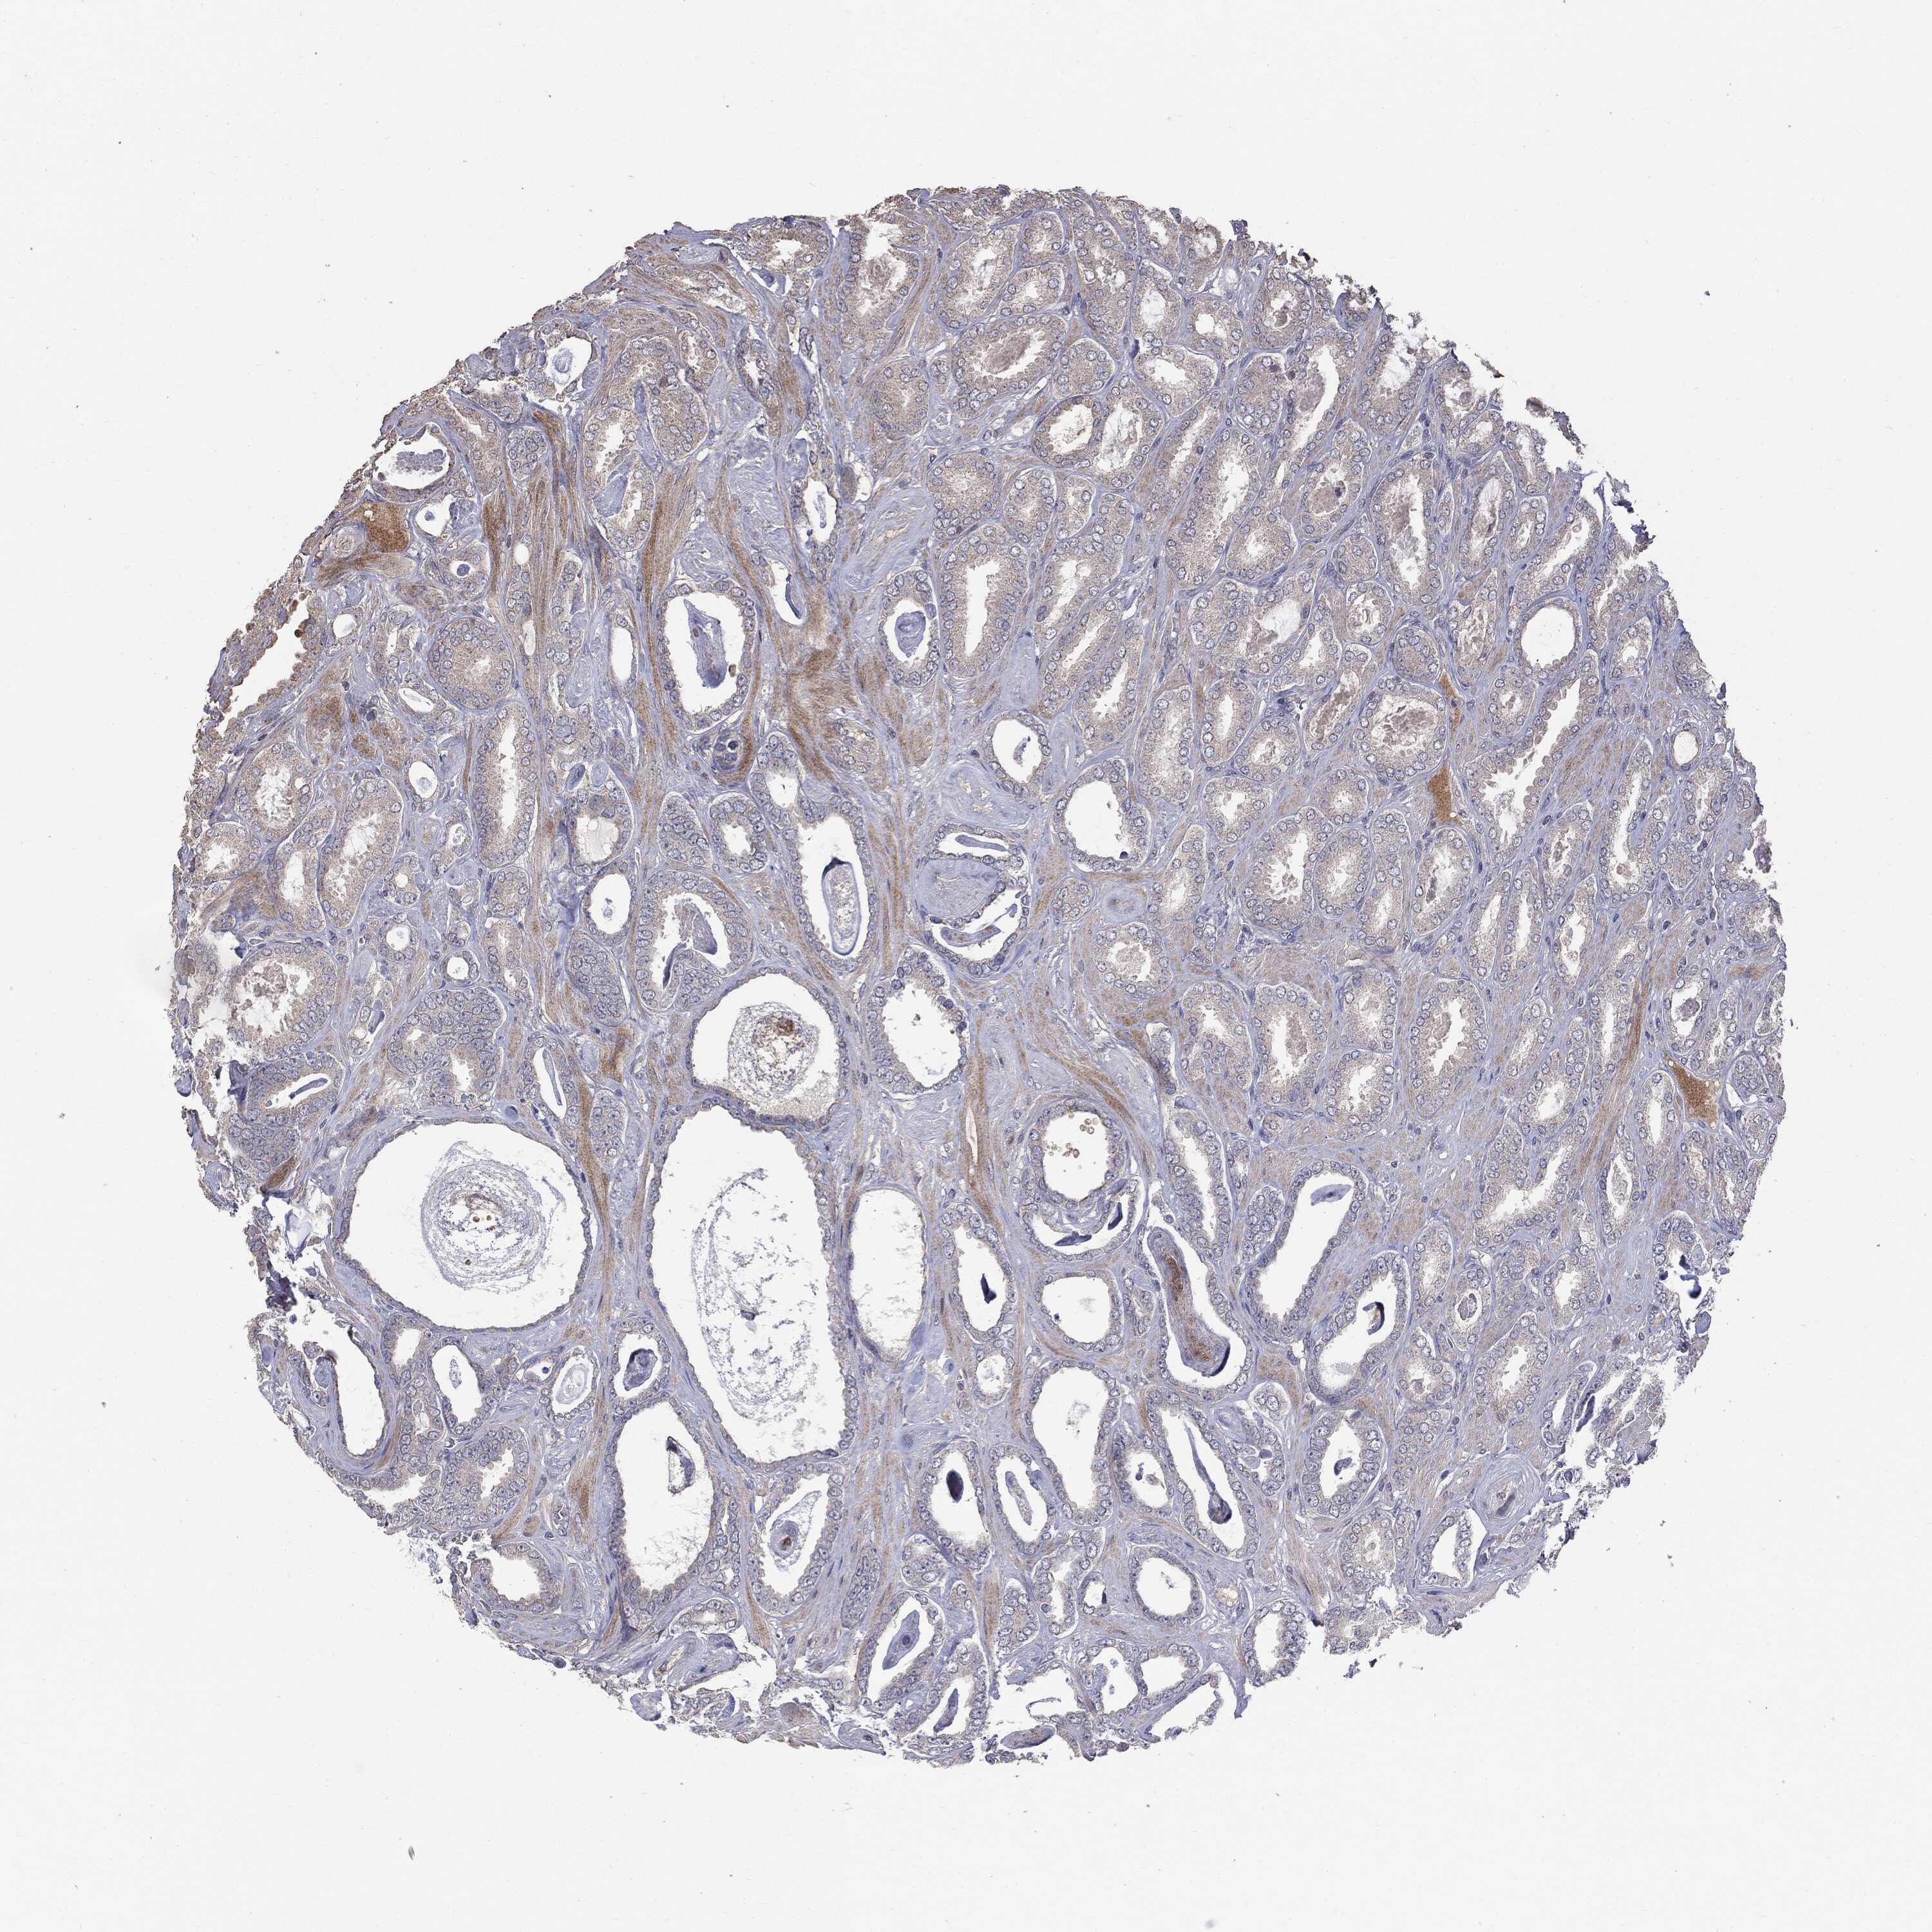

PROSTATE CANCER - Protein expressioni

A mouse-over function shows sample information and annotation data. Click on an image to view it in a full screen mode. Samples can be filtered based on level of antibody staining by selecting one or several of the following categories: high, medium, low and not detected. The assay and annotation is described here.

Note that samples used for immunohistochemistry by the Human Protein Atlas do not correspond to samples in the TCGA dataset.

Antibody stainingi

Antibody staining in the annotated cell types in the current human tissue is reported as not detected, low, medium, or high, based on conventional immunohistochemistry profiling in selected tissues. This score is based on the combination of the staining intensity and fraction of stained cells.

Each image is clickable and will lead to virtual microscopy that enables deeper exploration of all samples and also displays staining intensity scores, fraction scores and subcellular localization as well as patient and tissue information for each sample.

CAB069425

CAB080053

CAB080065

CAB080070

CAB080081

CAB080095

CAB080097

Staining

High

Medium

Low

Not detected

Intensity

Strong

Moderate

Weak

Negative

Quantity

>75%

75%-25%

<25%

None

Location

Nuclear

Cytoplasmic/membranous

Cytoplasmic/membranous,nuclear

Adenocarcinoma, High grade

Adenocarcinoma, NOS

Adenocarcinoma, Low grade